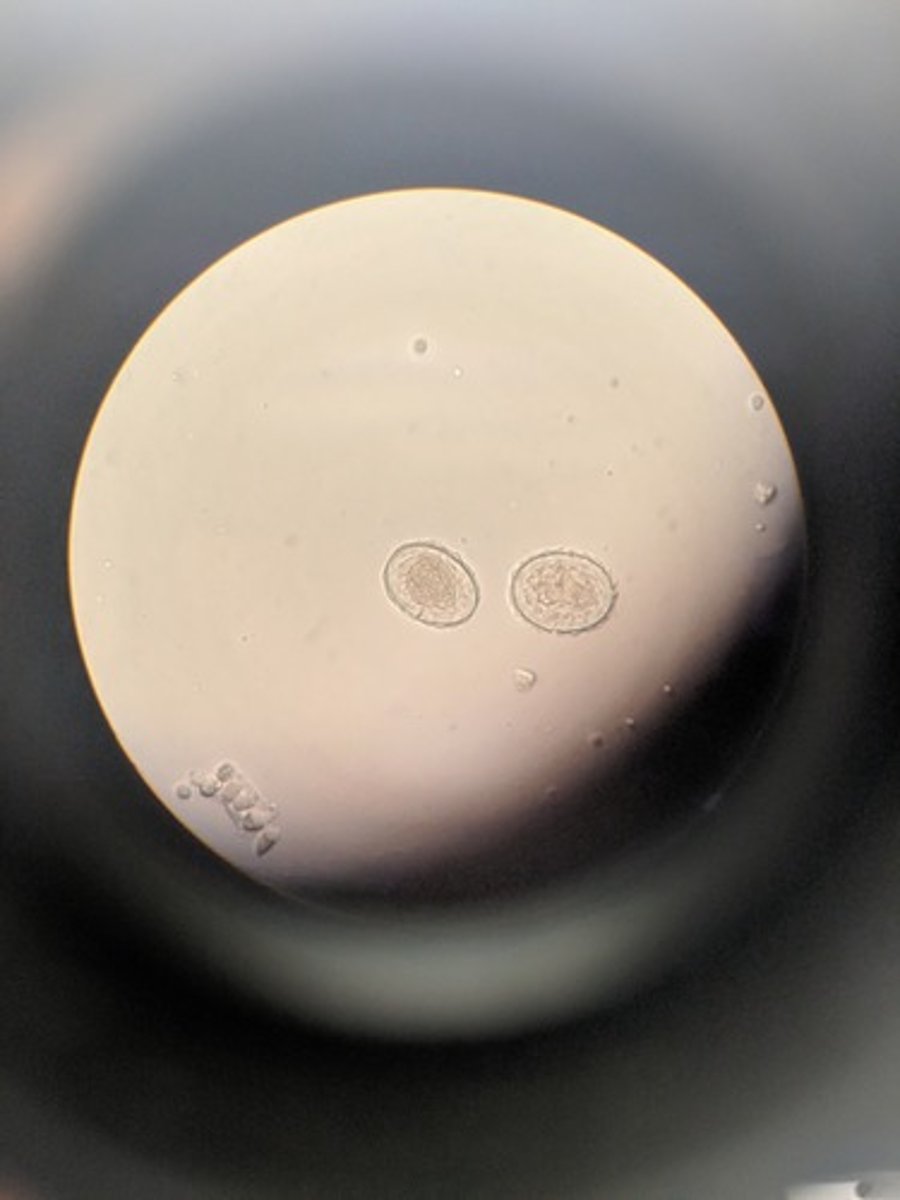

Balantidum coli cyst

Has double walled yeast cell